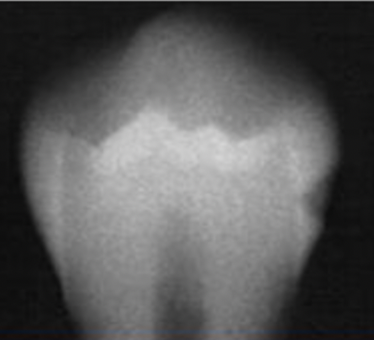

What is going on in the following radiograph?

Moderate occlusal caries